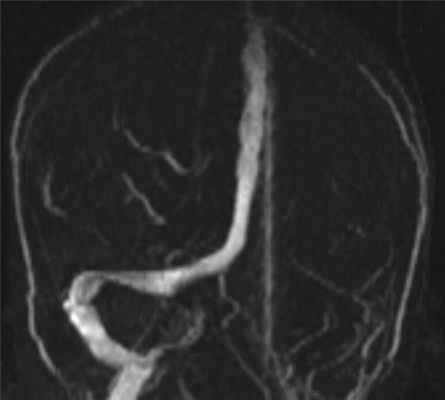

Наложены вторичные швы на заушные раны 16.10.14. В левую барабанную перепонку вставлен шунт, так как в барабанной полости скопился прозрачный экссудат. 25.10.14 проведена МРТ головного мозга, на которой выявлено сужение правой внутренней сонной артерии до 3 мм. На уровне вхождения в кавернозный синус на протяжении 10 мм кровоток не визуализируется (рис. 2). При контрольном осмотре через 1,5 мес самочувствие ребенка хорошее. В заушной области с обеих сторон линейный рубец. Из левого уха удален шунт, барабанная перепонка серая, опознавательные знаки есть, слух субъективно в норме. В правом ухе полость полностью эпидермизирована, сухая, шепотная речь 1—2 м.

Рис. 2. МРТ головного мозга в ангиорежиме от 25.10.14. 6 — левая нормальная внутренняя сонная артерия. Овальной линией выделено сужение правой внутренней сонной артерии; 7 — участок облитерации правой внутренней сонной артерии.